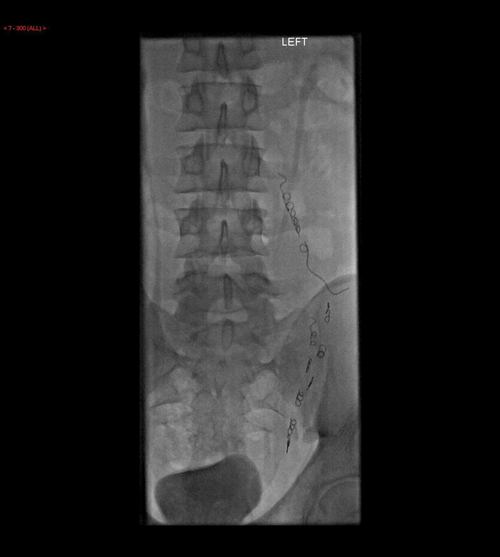

Figure 6: Static image showing the catheter in the left testicular

vein and contrast seen to outline the dilated vein.

Figure 7: Multiple coils are seen within the testicular vein at the end of the procedure.

Possible methods of treatment include sclerosing agents, metallic coils and detachable balloons. This is minimally invasive and has a faster recovery time compared with surgical repair and can be performed under local anaesthetic. The left spermatic vein is cannulated (Figure 6) and coils, or other material to be used, inserted and then the vein is reassessed to ensure the varicocele has been treated (Figure 7). Five to ten percent of varicoceles recur after embolisation and therefore it is recommended that patients undergo a routine ultrasound in approximately four weeks to ensure the varicocele has not returned.